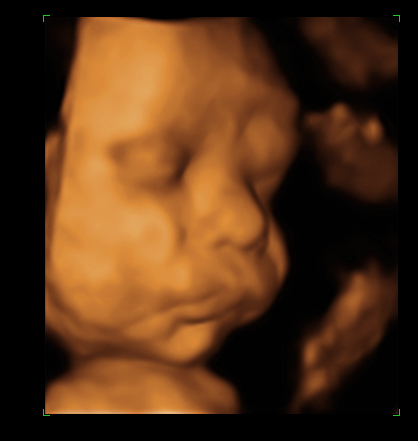

Наконец мы сделали это!!!Сегодня ходили на УЗИ.Малыш умничка, перевернулся головкой вниз)))А ещё был(а) безумно серьёзен и временами немного недоволен))))И мы сделали наши первые фотографии)))Моей радости просто нет предела!!!

а ещё у нас очень пухленькие щёчки)

недовольно трём глазки и морщимся))))